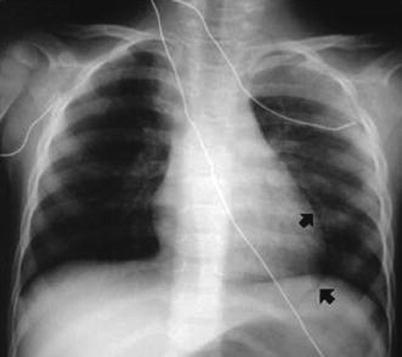

Fig. 15.4

Subtle anterior pneumothorax in anteromedial (superior black arrowhead) and subpulmonic (inferior black arrowhead) recesses

Pneumothoraces are common complications after penetrating thoracic injury and occur secondary to disruption of the alveoli and lung parenchyma leading to leakage of gas into the interstitial space. The most frequent radiographic finding is the “visceral-pleural line” (Fig. 15.3) in the apical-lateral lung field representing separation of the normally apposed visceral and parietal pleura. Pneumomediastinum is also frequently encountered and is most commonly due to pulmonary-alveolar rupture. These radiographic signs can vary from subtle findings to gross abnormalities. Trauma patients are often in the supine or semirecumbent position when the portable chest x-ray is acquired. In these positions, it has been reported that up to 30 % of pneumothoraces are not visualized. Patient positioning can be changed to increase radiographic sensitivity but is often not feasible in the trauma setting. Instead you should be aware of other places that the pneumothorax may be visualized, namely, the anteromedial and subpulmonic recesses (Fig. 15.4). Other less common imaging findings present with a pneumothorax include a hyperlucent upper abdomen, sharply demarcated diaphragm, demarcation of the inferior surface of the lung, and the “deep sulcus sign” (Fig. 15.3).